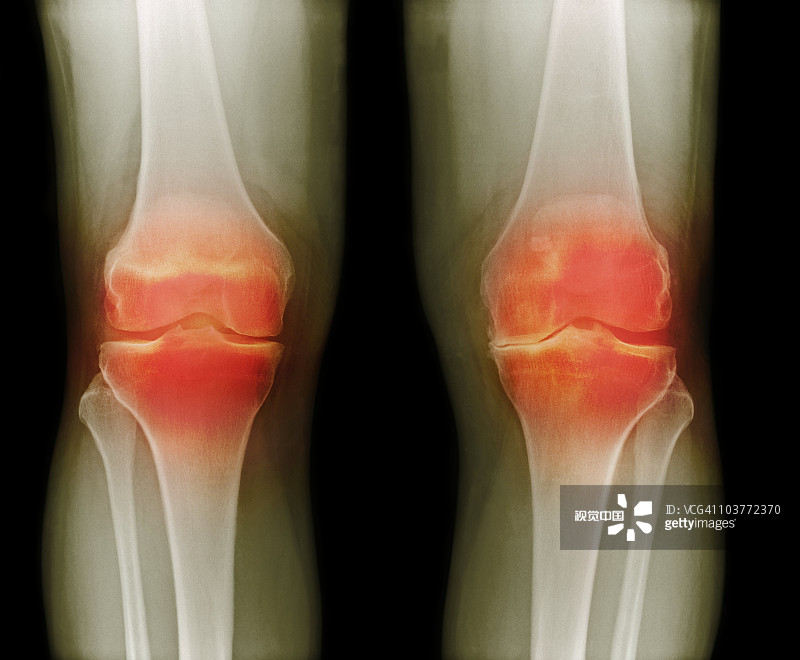

適應(yīng)癥:膝骨關(guān)節(jié)炎

貴醫(yī)附院 | 人臍帶間充質(zhì)干細(xì)胞治療膝骨關(guān)節(jié)炎患者的1期臨床試驗(yàn)

- 2.依據(jù)參考中華醫(yī)學(xué)會(huì)骨科學(xué)分會(huì)關(guān)節(jié)外科學(xué)組制定的“骨關(guān)節(jié)炎診療指南(2018年版)”,明確診斷為膝骨關(guān)節(jié)炎(KOA)

- 6.受試者研究側(cè)膝關(guān)節(jié)Kellgren-Lawrence分級(jí)為II/III級(jí)。